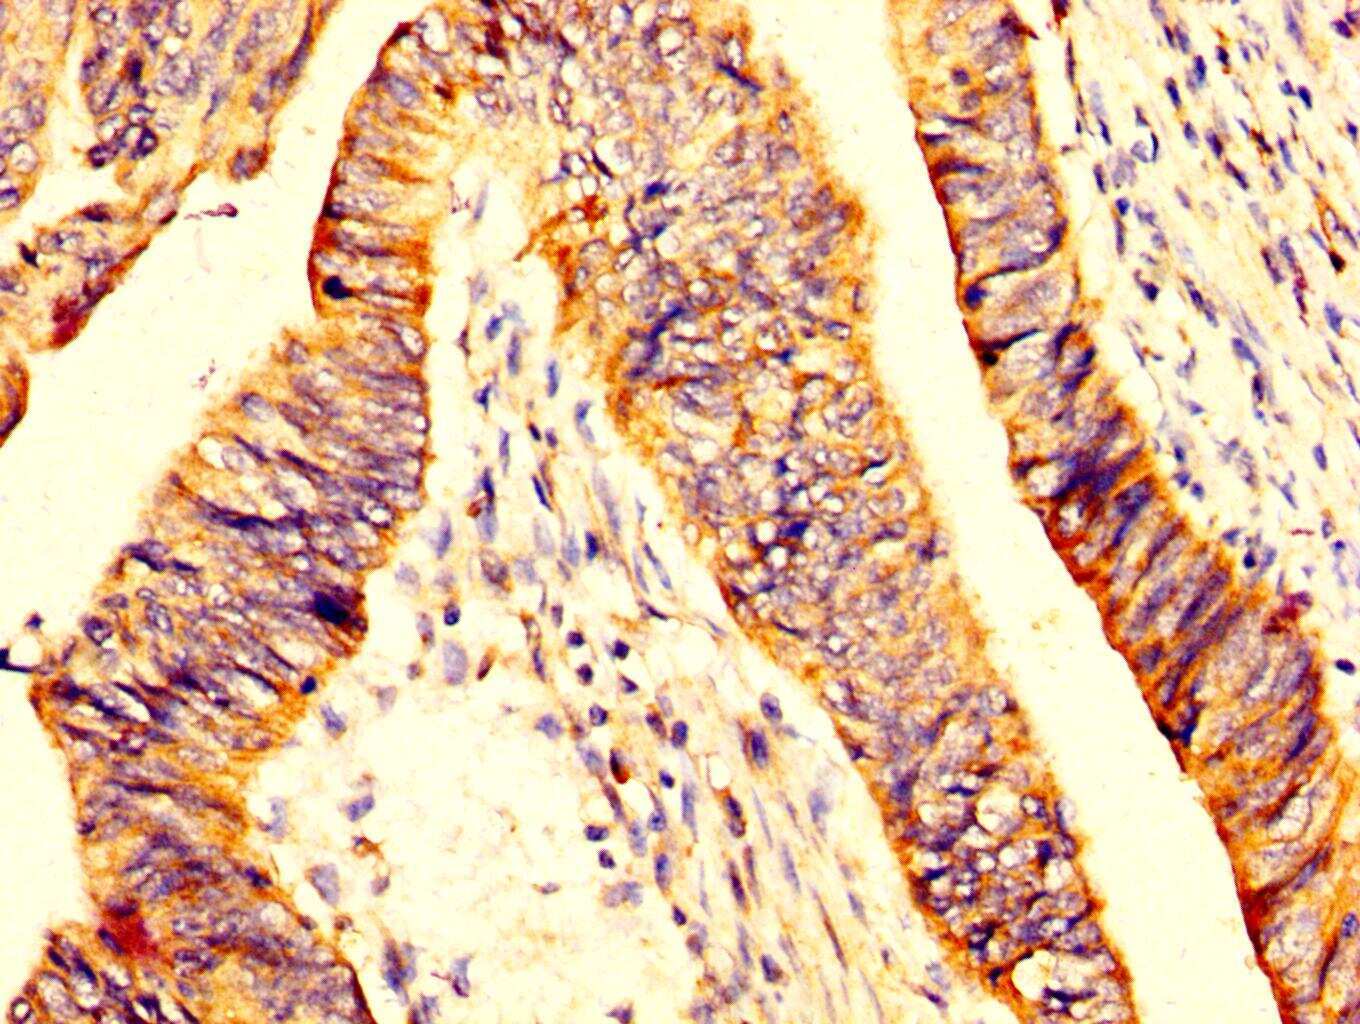

- Submitted by

- Invitrogen Antibodies (provider)

- Main image

- Experimental details

- Immunohistochemical analysis of MYOC in paraffin embedded human colon cancer using a MYOC polyclonal antibody (Product # PA5-98815) at a dilution of 1:200. After dewaxing and hydration, antigen retrieval was mediated by high pressure in a citrate buffer (pH 6.0). Section was blocked with 10% normal goat serum 30min at RT. Then primary antibody (1% BSA) was incubated at 4°C overnight. The primary is detected by a biotinylated secondary antibody and visualized using an HRP conjugated SP system.